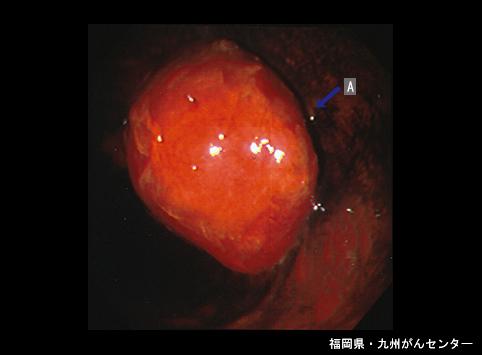

질환(병리주체)의 분류 악성 상피성종양/편평상피암

부위(장기별) 식도/중

검사방법 내시경

종양의 육안분류 1형(종괴형)/

종양의 최대경(밀리미터) 35~40

종양의 심달도 mp